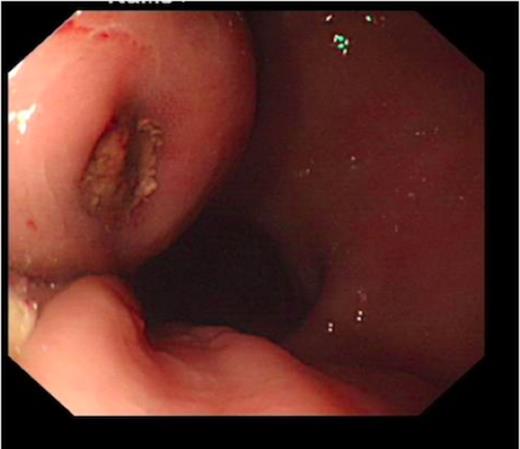

An endoscopy performed four years post-operatively demonstrated two atypical acute gastric ulcers in the distal stomach (figure 1), which were treated with a heat probe (figure 2). Two days later she presented as an emergency in hypovolaemic shock following a large volume haematemesis (haemoglobin of 40g/l). An urgent upper gastrointestinal endoscopy revealed a visible vessel at 35 cm forming part of an expansive mass within the gastric conduit. EUS demonstrated a heterogeneous mass indenting the gastric conduit, containing a strong Doppler signal (figure 3). An urgent computerised tomography (CT) angiogram revealed a Type-A thoracic aortic aneurysm with an enteric fistula (figure 4). The saccular aneurysm of the thoracic aorta was embedded in the gastric conduit. A 28x16cm Valiant® (Medtronic Ltd, Minneapolis, USA) stent was placed in the descending thoracic aorta with good occlusion of the aneurysm. The patient made an excellent recovery and was discharged on the seventh day post stenting.

Erosion of the gastric conduit by highly acidic gastric contents may also predispose to fistula formation (3). Gastric erosion and ulceration into both the aorta and pericardium from the intra-thoracic portion of the stomach has been reported post oesophagectomy. A reduced blood supply to the gastric conduit may predispose to gastric erosion. It is further proposed that chronic infection of these gastric ulcers may be a contributory factor. Pathological sections of aorta-oesophageal fistula have shown a granulomatous type inflammation suggestive of mycotic infection complicating ulceration (3). Indeed this may well have been the cause of the fistula in the case report we have described. An endoscopy performed two days prior to the presentation of the aorto-oesophageal fistula showed two acute atypical looking gastric ulcers.